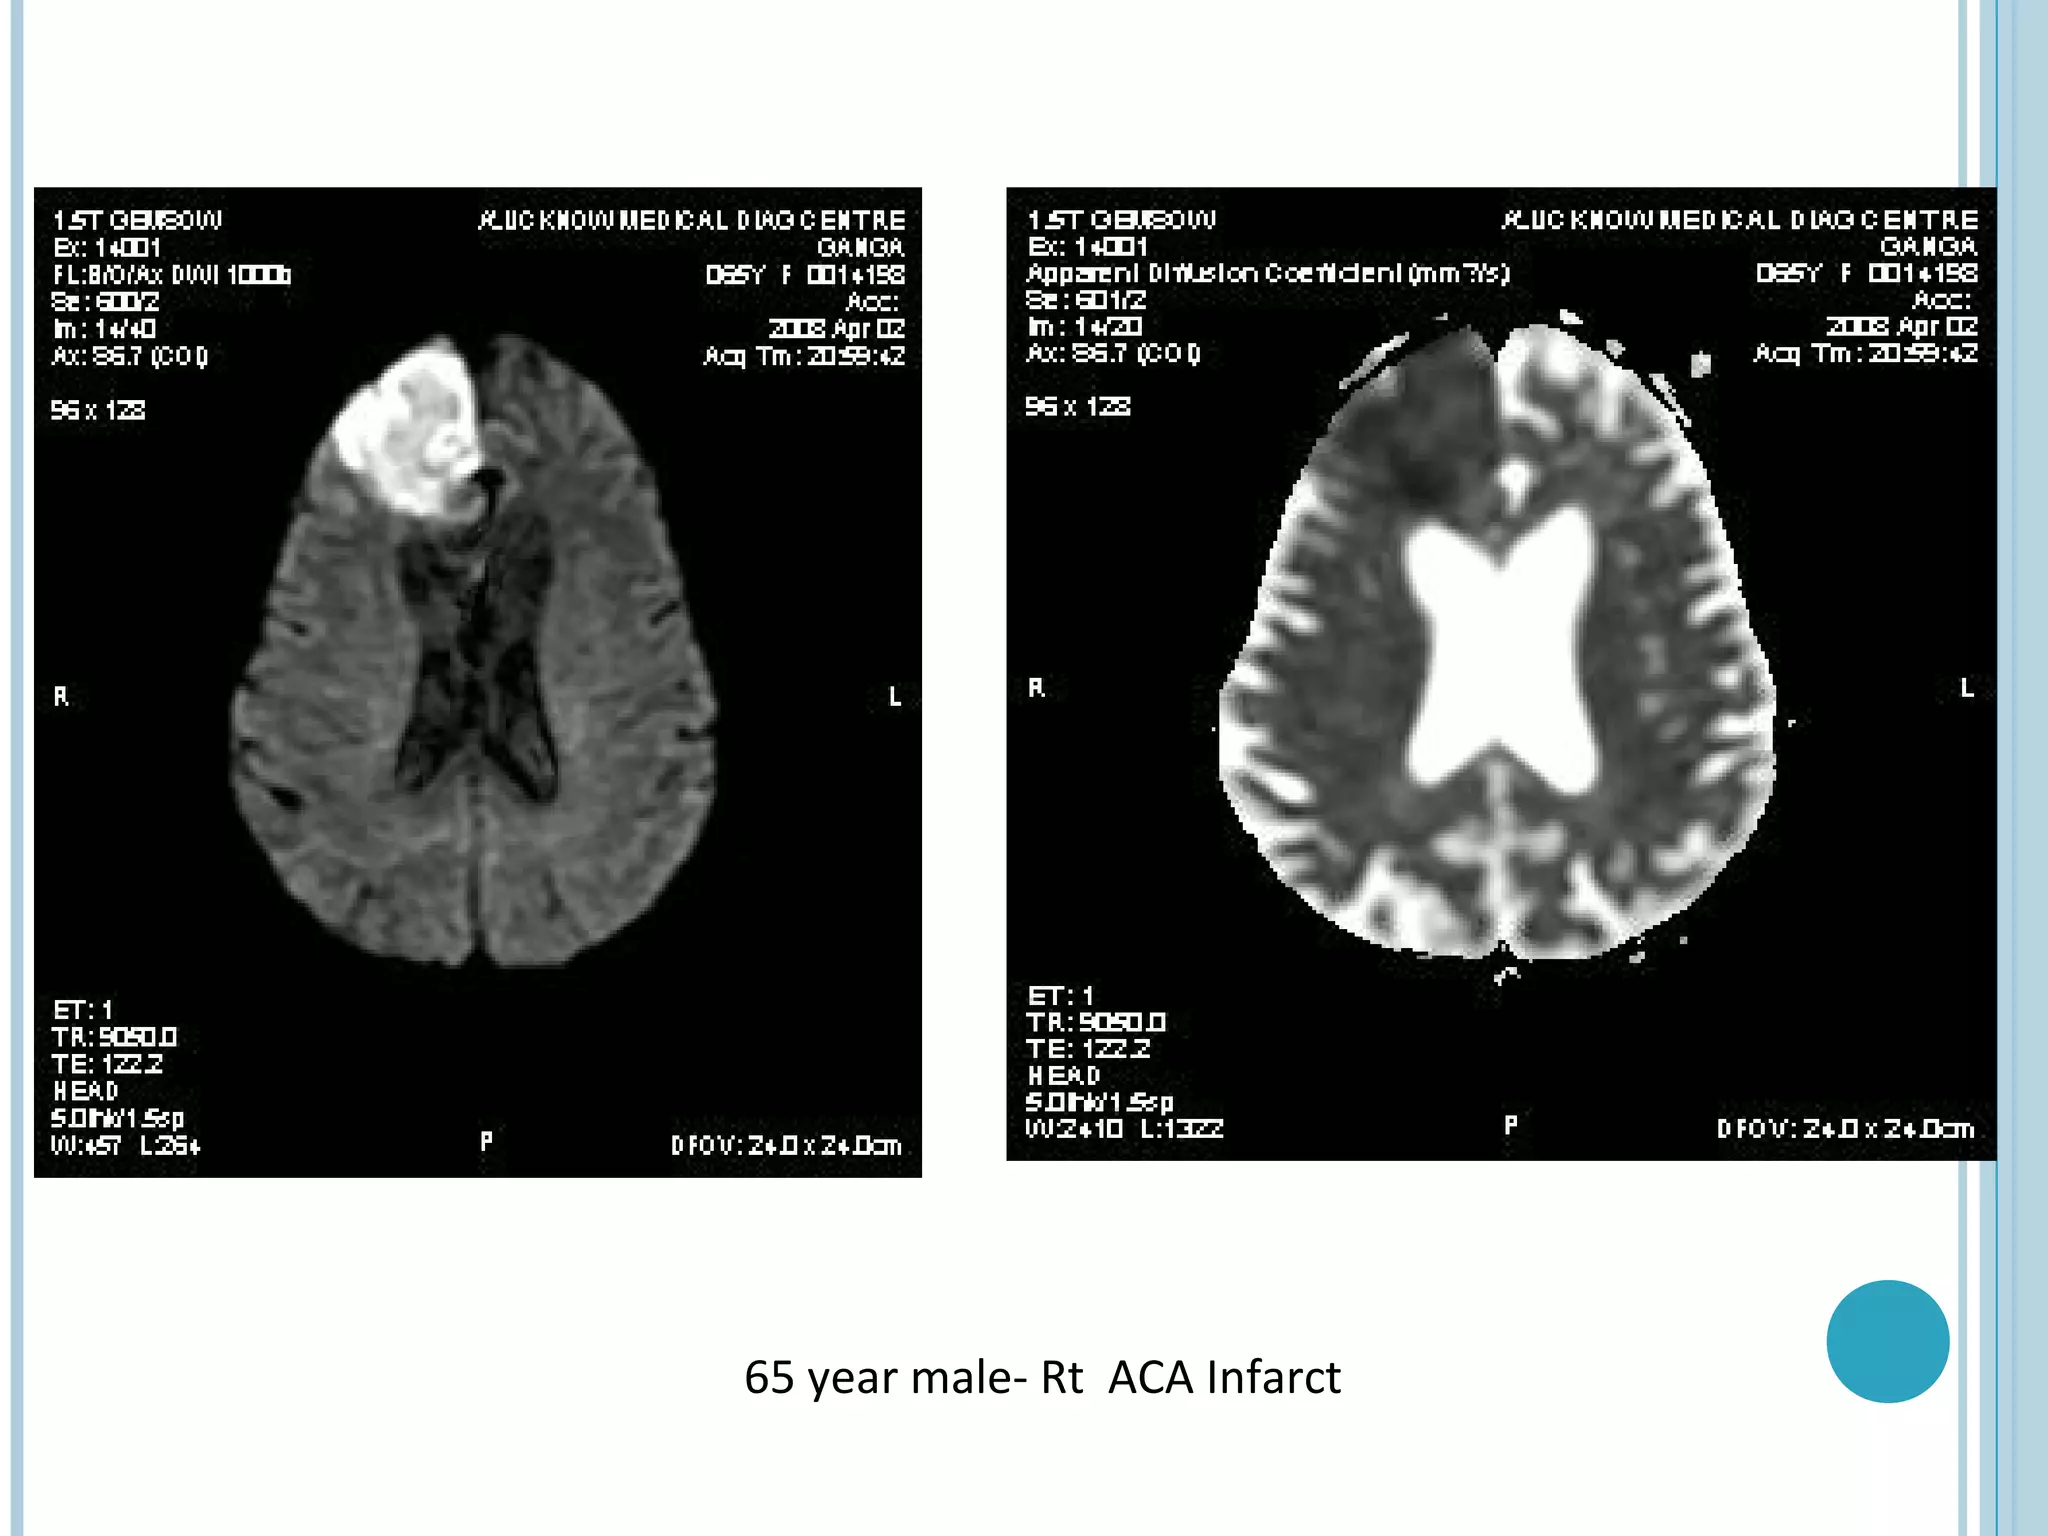

65 year male- Rt ACA Infarct

65 year male-Rt ACA Infarct